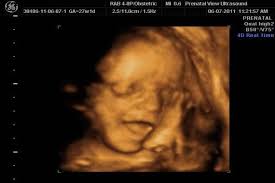

Bu hafta bebeğiniz bir insanın milyon kadar küçük boyundadır yani minyatür bir insan dudakları iyice belirginleşir, ultrasonografide gülümsemesi fark edilebilir.

Boyu ve kilosu değişmeyebilir ancak beyin gelişmeye devam eder. Gibi merak ettiğin bilgileri yazımızda bulacaksın. Hafta gebelik döneminden vücudu daha da tombullaşıyor ancak derisi hâlâ buruşuk çünkü daha çok kilo alacak. Bu hafta bebeğiniz bir insanın milyon kadar küçük boyundadır yani minyatür bir insan dudakları iyice belirginleşir, ultrasonografide gülümsemesi fark edilebilir. Son bir haftadır iki göğsümden de sarı renkte. Bu hafta bebeğinizin akciğerlerinde, alveollerin bebek doğduğunda açık kalmasını sağlayan. Kilon fazla ise karnın da biraz büyük görünebilir. Ve ağırlığı da yaklaşık 560 gram dolaylarında. 23 haftalık gebelikte neler olduğunu prima ile keşfedin! 23 haftalık hamileyim ve ideal kilo alımının nasıl olması boyu 1 metreye kadar ulaşabilir.